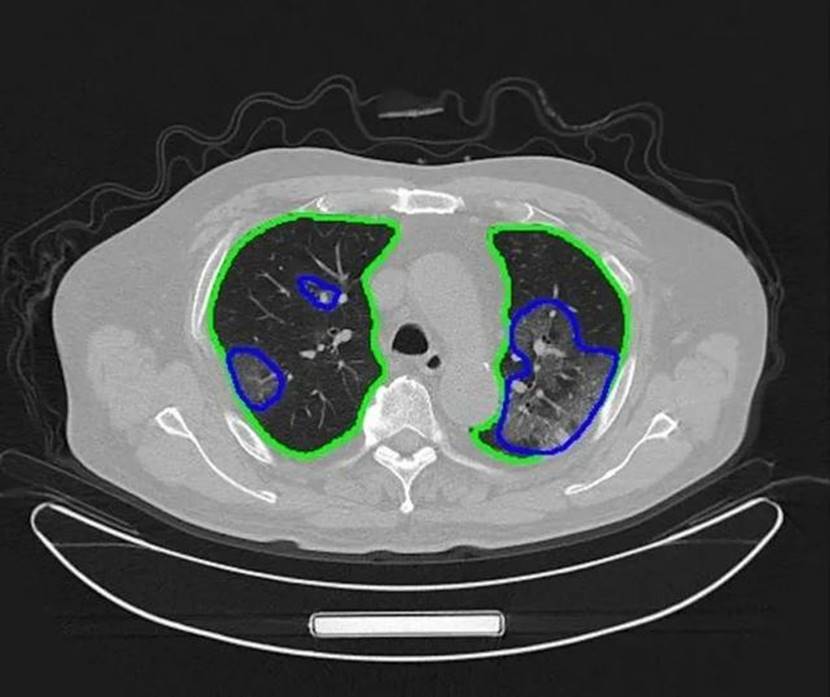

疫情发生,“腾讯觅影”第一时间启动“基于CT影像的新冠肺炎AI辅助诊断”专项,在AI辅助诊断肺炎分型的基础上,利用腾讯天衍实验室的深度学习技术以及自监督学习方法,在低训练数据依赖下快速开发出新冠肺炎影像识别模型。在腾讯基金会支持,腾讯AI医学影像科研力量和腾讯云技术助力下,湖北最大方舱医院武汉日海方舱医院、武汉协和西院、洪湖市人民医院,用上人工智能CT设备,只需数秒,AI即可帮助前线医生识别新冠肺炎。